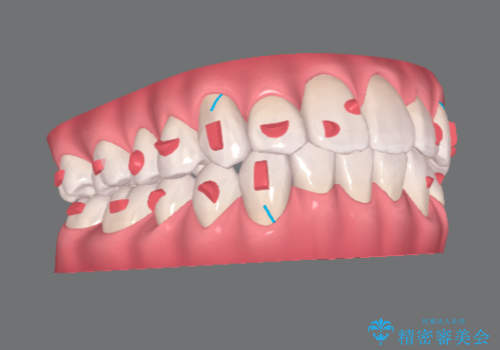

インビザライン で治す 出っ歯の治療

- 前歯の突出感、出っ歯の治療を希望され来院されました。

インビザラインを用いた治療計画を立て、しっかりと出っ歯を治すためにマイクロインプラントを併用します。

マイクロインプラントを併用することでしっかりとマウスピース全体を後方へ引き、前歯の突出感を改善することができました。